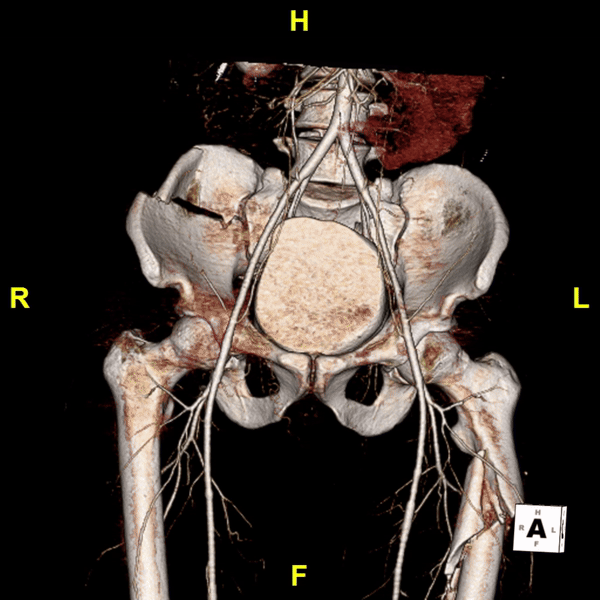

Figure D: A 3D reconstruction of the pelvis shows a comminuted fracture of the right iliac wing with extension into the sacroiliac joint, and nearby vascular structures.